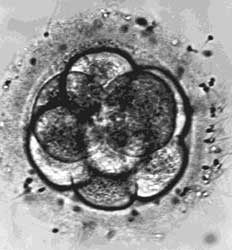

Αμερικανοί ερευνητές που εργάζονται στην κλωνοποίηση ποντικών δημοσίευσαν, στην επιστημονική επιθεώρηση Cell, τα αποτελέσματα της τελευταίας τους έρευνας, σχετικά με το πώς στελεχιαία κύτταρα που παράχθηκαν από κλωνοποιημένα έμβρυα, μπορούν να χρησιμοποιηθούν για τη θεραπεία ασθενειών